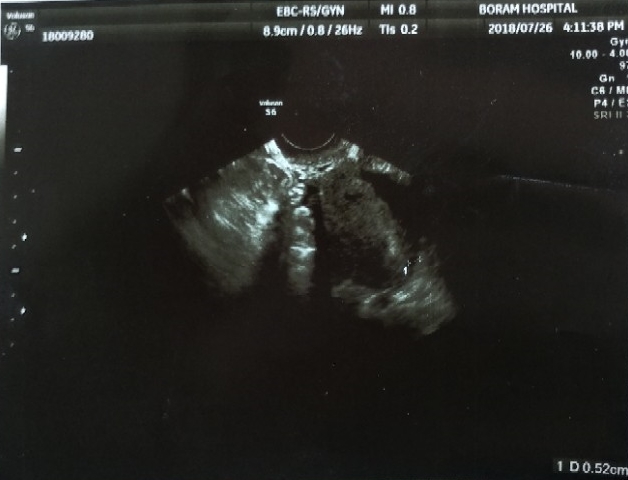

심쿵이 초음파사진(4주-12주)/세이베베

2018.07.26 (4주 3일) 첫 임신 확인 한 날! 이때는 완전 점만큼 작았던 심쿵이 2018.08.06 (6주) 심쿵이 첫...